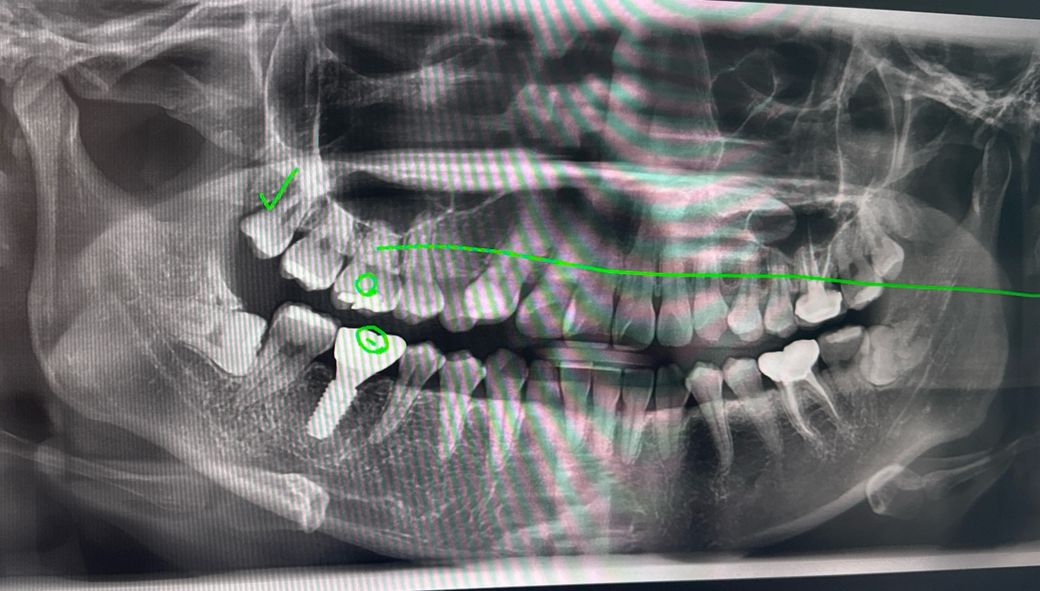

아프지 않은 완전매복사랑니 빼야하나요?

윗 사랑니 두개는 밖으로 나와서 오늘 빼고 왔습니다

밑사랑니가 2개다 잇몸속 완전 매복되어있는데 아프거나하진 않아요. 근데 빼는게 좋을까요? 20대인데 벌써 임플란트가 1개 있어서 치아관리 좀 잘하려고요

아래 사랑니는 옆으로 누워있는 수평매복 사랑니입니다. 수평매복 사랑니는 바로앞 어금니를 상하게 하니 가능한 빨리 배는 것을 추천합니다. 그냥두면 나중에 바로앞 어금니와 사랑니를 같이 빼야 하는 경우가 발생할 수 있습니다.

매복사랑니의 경우 옆 어금니의 치아뿌리를 흡수하거나 뿌리 충치를 유발할지에 따라 빼는것이 나을지 가늠해보게 됩니다

지금으로서는 꼭 빼야하는 상황은 아닌것으로 보입니다